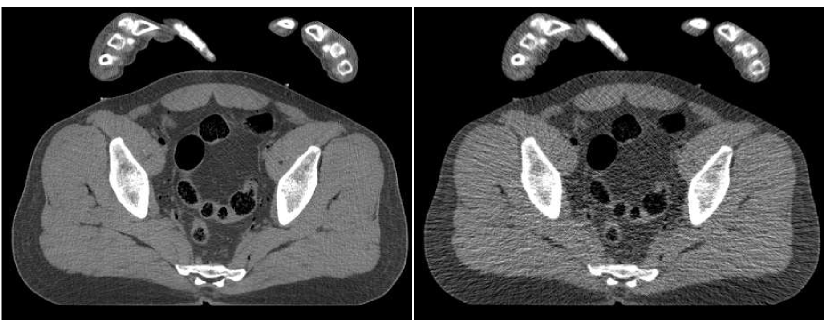

In Figure 6 we present a reconstruction of a test image. This test image is taken cm away from the region where the training data was taken from. The middle upper image is the result of a fusion of the number of FBP versions, performed with the trained ANN. By the visual impression, the noise-resolution balance in the fused image is better than in any of the FBP versions forming it. The texture of tissues is closer to the original (observed in the reference image, upper left). The level of streaks and general noise are lower than in the central and right FBP images, and the image sharpness is higher than in the left and the central images. Thus, the fusion image enjoys the good properties offered by each of the FBP versions and is superior than any of them.

Recall that the training was done with a set of weights, corresponding to our penalty component from Equation IV-C. The quantitative error measures we compute for this comparison include plain SNR, SNR weighted by those weights, the training risk and the SSIM measures. These values are given in Table I. As observed from the table, the weighted SNR of the fusion image is dB higher than the highest attainable value in FBP images. For plain SNR this increment is dB. Values of the training risk measure behave expectedly: the weights of ANN training were designed to implicitly reduce this measure for the fusion image. Indeed, it is by lower than that of the optimal FBP image. Finally, the SSIM measure supports the claim the fusion image has the best visual appearance, since it admits the larger value for this measure.